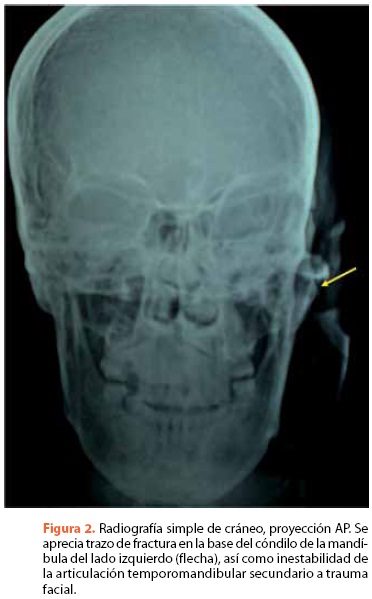

El diagnóstico por imagenología para valoración de los TTM puede estar dirigido al estudio del tejido óseo (figuras 2 y 3) o de tejidos blandos. Serán necesarias técnicas que proporcionen imágenes adecuadas de los tejidos duros para el diagnóstico de fracturas, alteraciones por interferencia discal, alteraciones degenerativas, hipomovilidad crónica o trastornos del crecimiento. No obstante, si existen trastornos por interferencia discal, daño discal o alteraciones inflamatorias, serán también necesarias técnicas de imagen que permitan observar los tejidos blandos.

Las técnicas radiológicas habituales para el estudio de las estructuras óseas de la ATM son la ortopantomografía y las proyecciones radiográficas submentovertex y transcraneales, que permiten evaluar la posición e integridad de los cóndilos. Para un estudio más detallado de la morfología de las estructuras óseas, en caso de haber detectado alteraciones clínicas o radiográficas que lo indiquen, es preciso emplear técnicas tomográficas, principalmente tomografía computadorizada y resonancia magnética las cuales ofrecen una representación excelente del disco articular y tejidos blandos de la ATM, permite diagnosticar alteraciones de la posición, integridad o movilidad discal, proliferaciones sinoviales, cambios óseos degenerativos, inflamación retrodiscal, hemorragias, cuerpos libres, tumores, etcétera18.